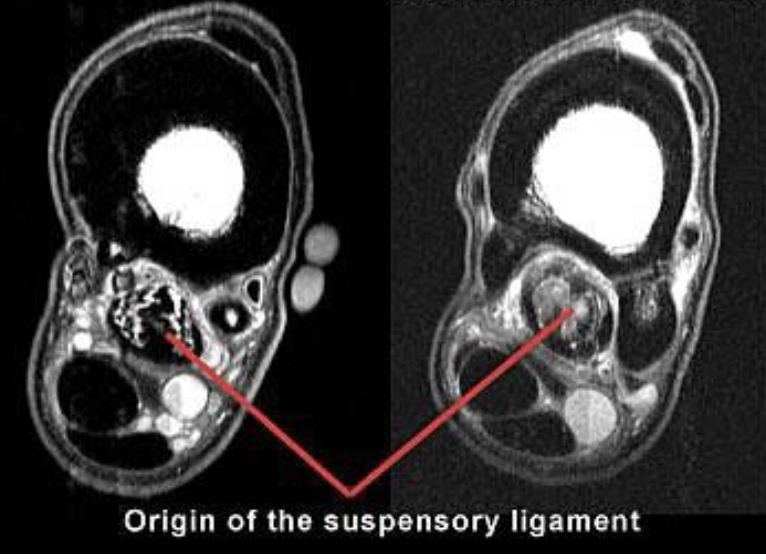

what is this

left= normal

right= suspensory ligament desmitis

cloudyness (red arrow) is showing fluid injury

white lines on left image is normal for comparison

what is this

suspensory ligament desmitis

green is surrounding tear

on left side of MRI, bulging out is visible, hitting neurovascular bundle and causing pain